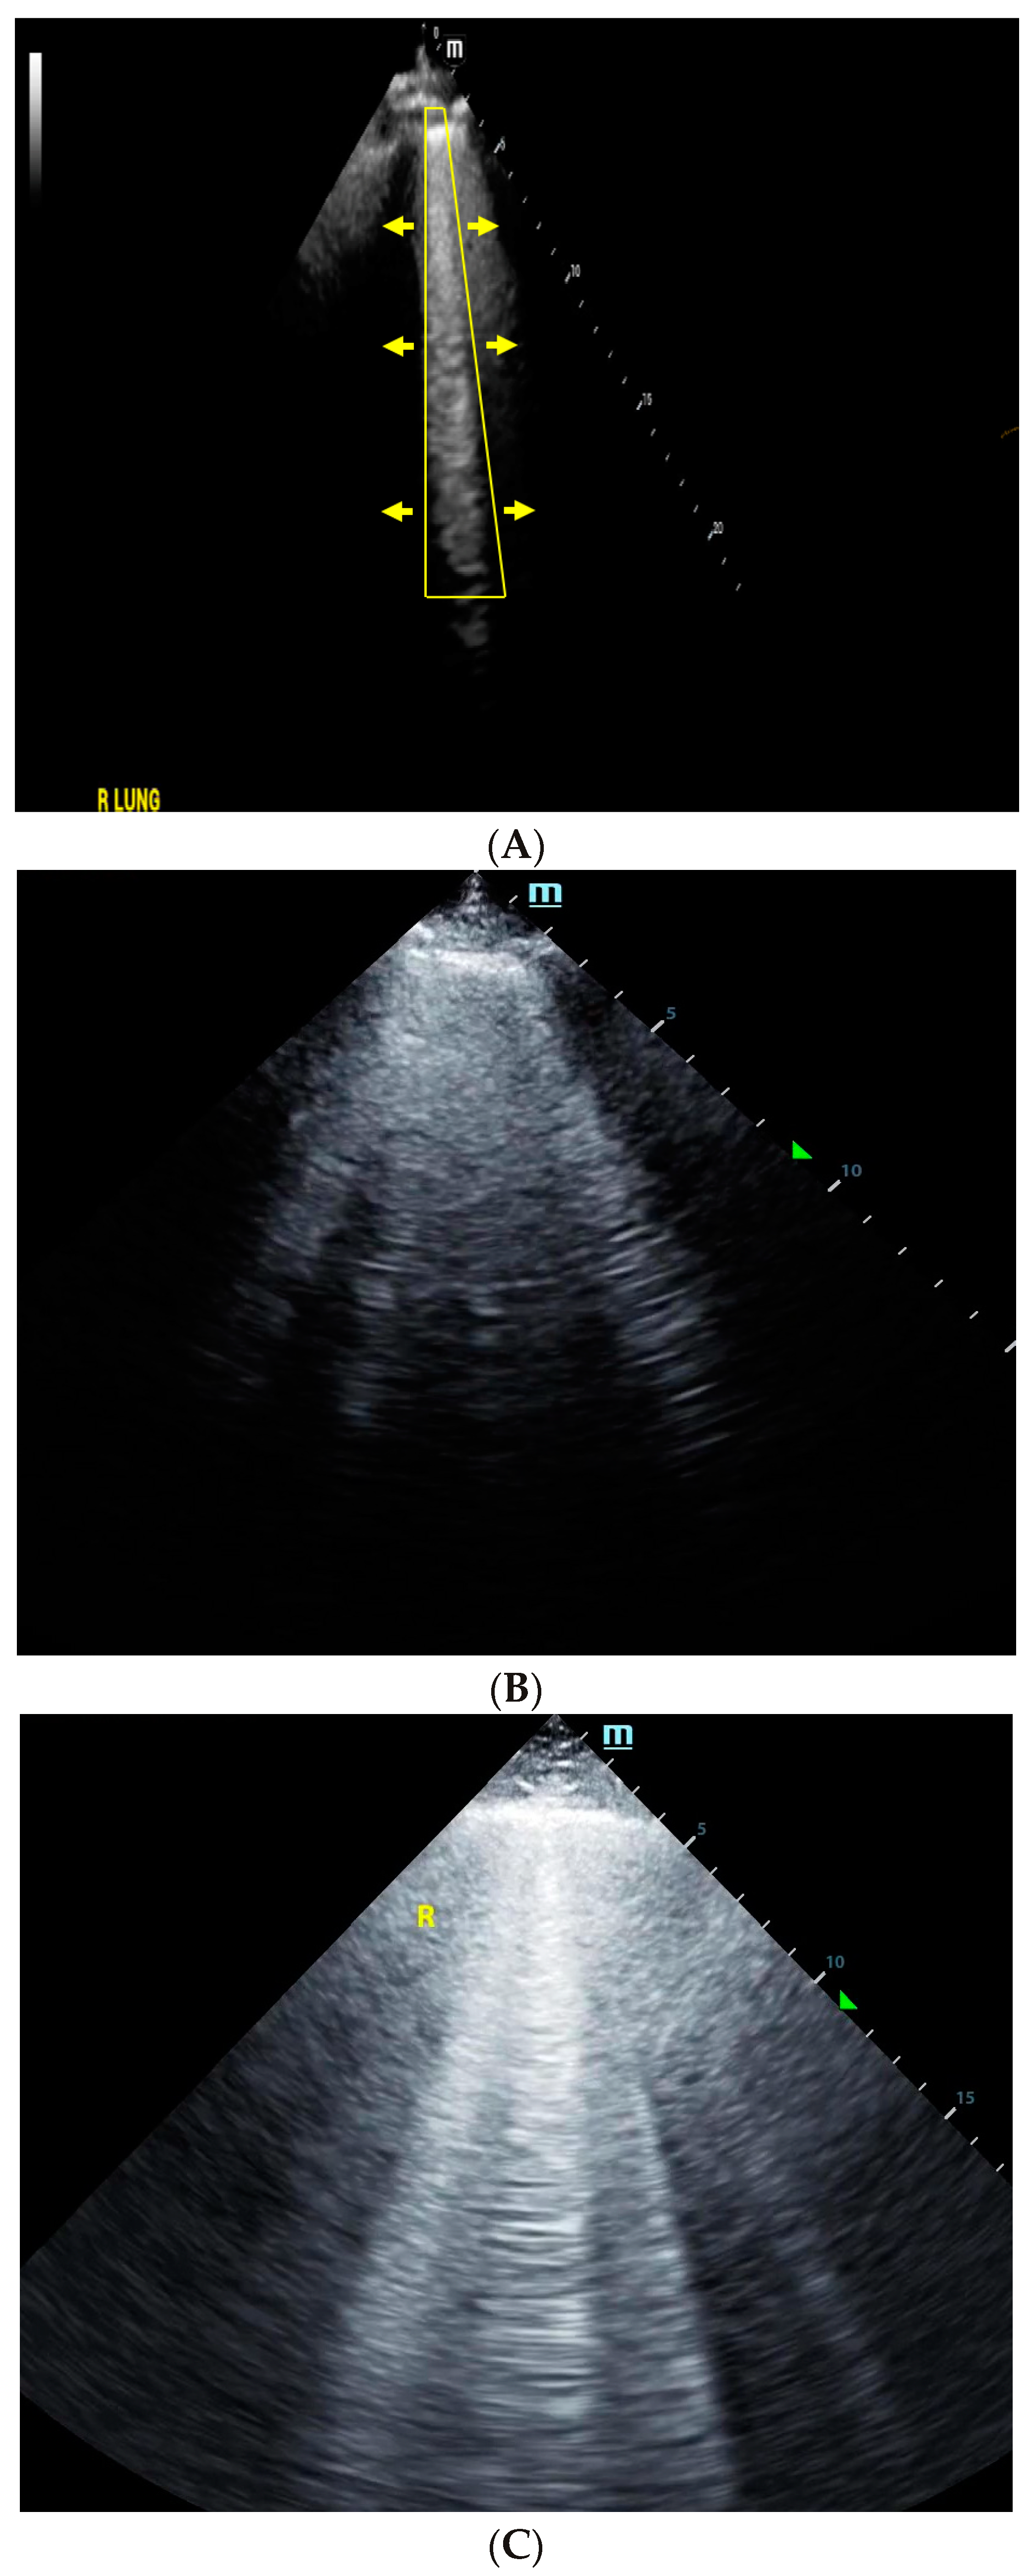

4. Lung Ultrasound

- Volpicelli, G.; Elbarbary, M.; Blaivas, M.; Lichtenstein, D.A.; Mathis, G.; Kirkpatrick, A.W.; Melniker, L.; Gargani, L.; Noble, V.E.; Via, G.; et al. International evidence-based recommendations for point-of-care lung ultrasound. Intensive Care Med. 2012, 38, 577–591. [Google Scholar] [CrossRef]

- Lichtenstein, D.A.; Meziere, G.A. Relevance of lung ultrasound in the diagnosis of acute respiratory failure: The BLUE protocol. Chest 2008, 134, 117–125. [Google Scholar] [CrossRef] [PubMed]

- Lichtenstein, D.; Meziere, G.; Biderman, P.; Gepner, A.; Barre, O. The comet-tail artifact. An ultrasound sign of alveolar-interstitial syndrome. Am. J. Respir. Crit. Care Med. 1997, 156, 1640–1646. [Google Scholar] [CrossRef]

- Agricola, E.; Bove, T.; Oppizzi, M.; Marino, G.; Zangrillo, A.; Margonato, A.; Picano, E. “Ultrasound comet-tail images”: A marker of pulmonary edema: A comparative study with wedge pressure and extravascular lung water. Chest 2005, 127, 1690–1695. [Google Scholar] [CrossRef]